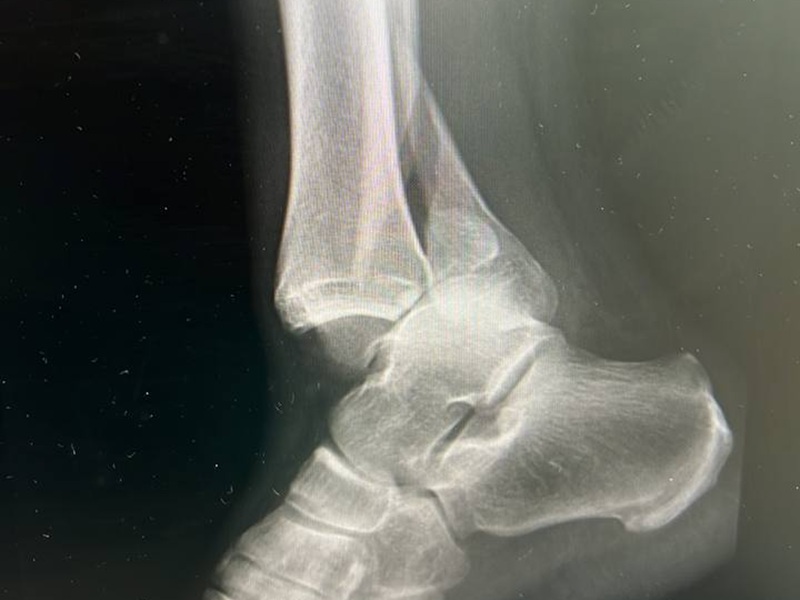

Металоостеосинтез МОС гомілки ДО-ПІСЛЯ